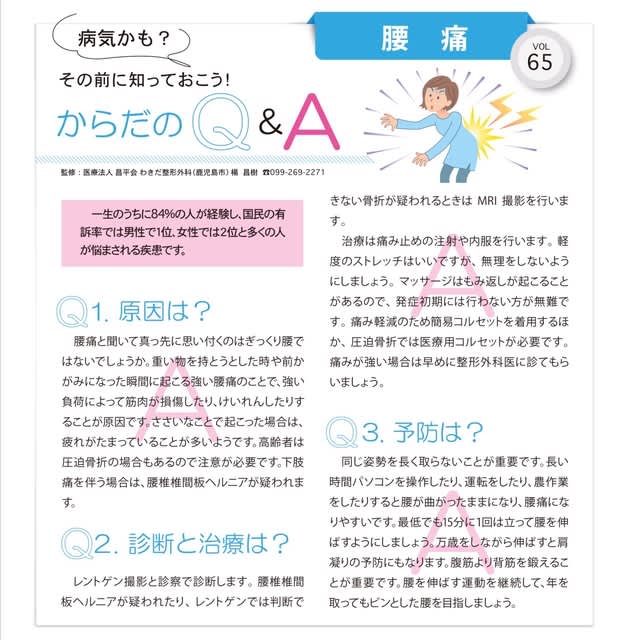

南日本新聞の生活情報誌てぃーたいむ 2019年5月号に寄稿させて戴きました。

腰痛(ぎっくり腰)についてです。

是非お読みください。